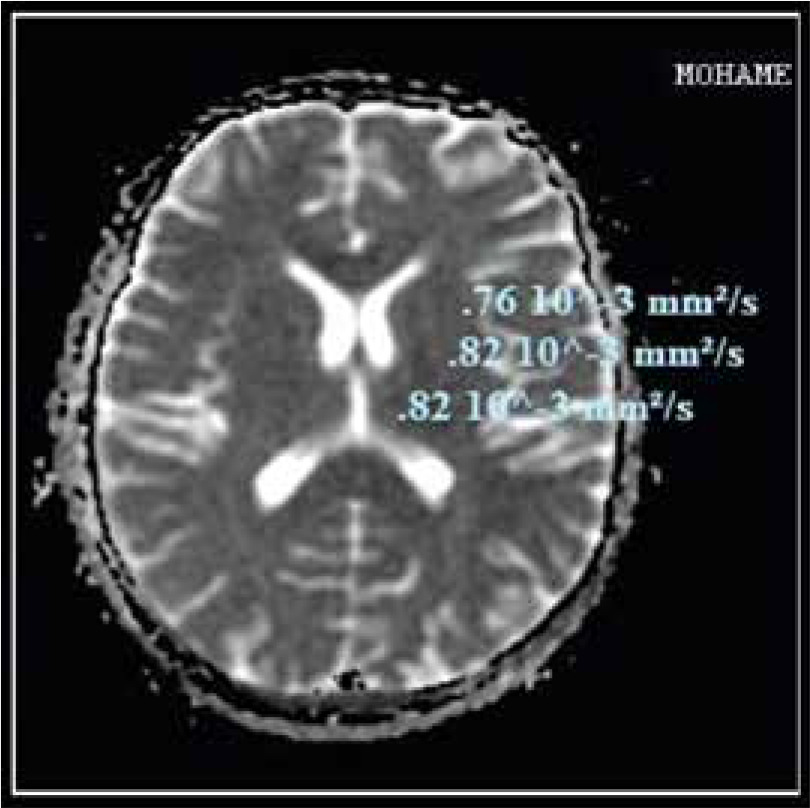

Compared to the control group, the ADC values of cirrhotic patients with HE were significantly higher. There were no significant differences between cirrhotic patients with MHE and those with overt HE in different brain regions. As shown in Table 5 and Figures 3 and 4, there was no statistically significant difference in ADC values between brain regions.

Fig. 4

Apparent diffusion coefficient (ADC) values in different brain regions in cirrhotic patient with overt hepatic encephalopathy (HE)